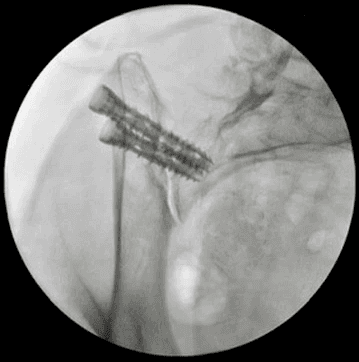

Posterior oblique Lateral